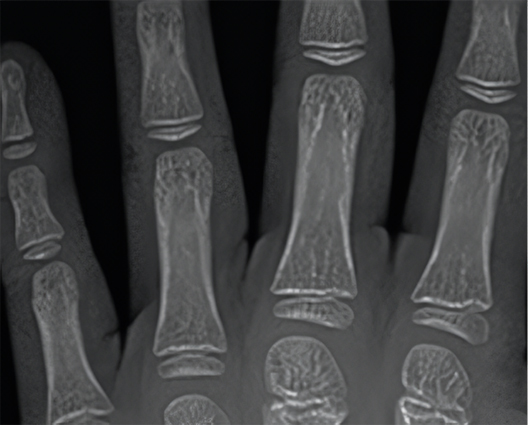

• Open Growth Plate